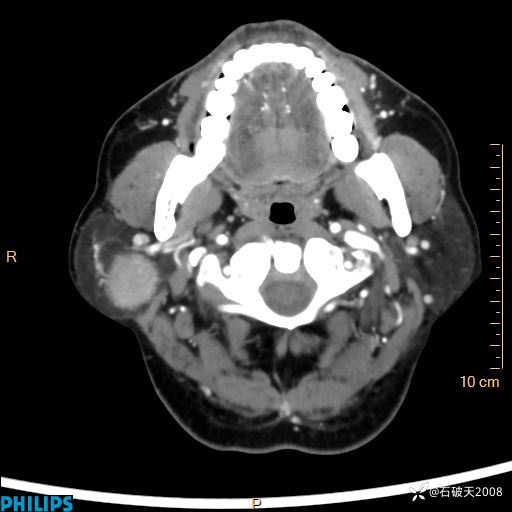

病例分享:颈部占位,一周后公布病理

男 57岁 主 诉:发现右侧颌下肿物1月余。

现病史:1月余前家属发现右侧颌下肿物。局部皮肤无红肿、热痛,无吞咽困难,无异物感,无恶心、呕吐,无头痛、头晕,无胸闷、胸痛,无发热、咳嗽、咳痰及呼吸困难。于我院行体表肿块彩超检查(2024.03.15我院)示:右侧耳下皮下软组织内低回声,未治疗。今为进一步治疗门诊以“腮腺肿瘤”为诊断收住我科,发病来患者神志清,精神可,饮食、睡眠及大小便正常,体重无明显下降。

平扫